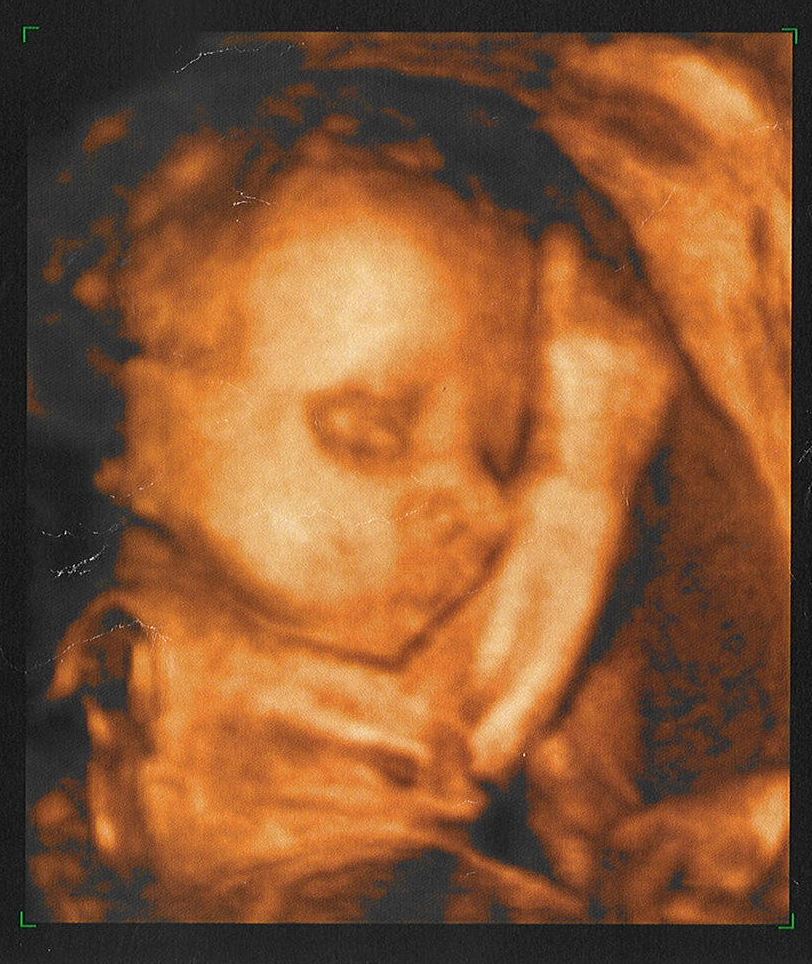

嗨!我已住在媽媽的子宮裡半年有多了,體積比之前膨脹了幾百倍!全賴媽媽一直悉心安胎孕育,讓我逐漸成長,現在我整個身體已成形,四肢也長出來了,內臟機能一切正常,只是眼睛還未看得見東西。除了感覺之外,我還開始有意識,聽覺倒是最靈敏的了。哈,爸媽又在討論着我了:「你猜他是男還是女?」「只要是我們的孩子,男女也沒所謂。」每次說完,媽媽總是開懷地笑,笑得肚內羊水翻湧,使我全身震盪。我於是伸手摸摸自己,噢,我是個男孩子啊!我想告訴他們,奈何不能。

因我長時間俯伏在媽媽的肚內,間中也需要舒展一下手腳,有時無意間會將拳頭或腳掌撐起了她的肚皮,形成一個隆起的小丘。媽媽會「哎吔」叫一聲,用手掌溫柔地搓幾下那凸起的地方,然後輕輕對我說:「好孩子,乖吧!」於是我便將手腳縮回。媽媽知道我聽從她,往往開心不已。